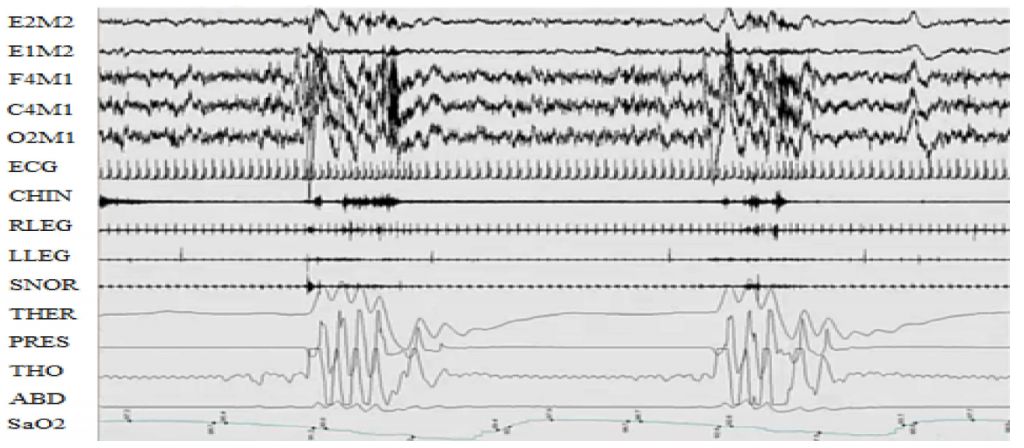

66.下圖為3分鐘睡眠記錄所顯示之呼吸事件為何者?(圖中頻道由上往下依序為E2-M2,E1- M2:眼動圖;F4- M1,C4-M1,O2- M1:腦電圖;ECG:心電圖;CHIN:頦下肌電圖;RLEG,LLEG:前脛骨肌電圖; SNOR:鼾聲;THER:口鼻溫度呼吸氣流;PRES:鼻腔壓力呼吸氣流;THO:胸部呼吸動作;ABD:腹部 呼吸動作;SaO2:血氧飽和度。) (A)中樞型呼吸中止 (B)阻塞型呼吸中止 (C)混合型呼吸中止 (D)陳氏呼吸